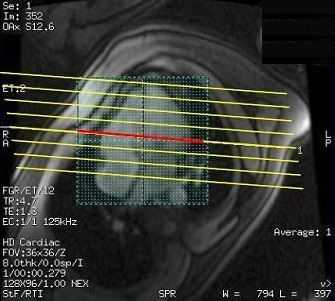

4. Place the parallel slices or single slice over the area of interest.

• To optimize the gated 2D FIESTA prescan enhancement, the intersection of the shim volume and slice locations should only be placed over the anatomy of interest.

Figure 2. Correct intersection and placement of shim volume and slice locations

Figure 3. Incorrect intersection and placement of shim volume